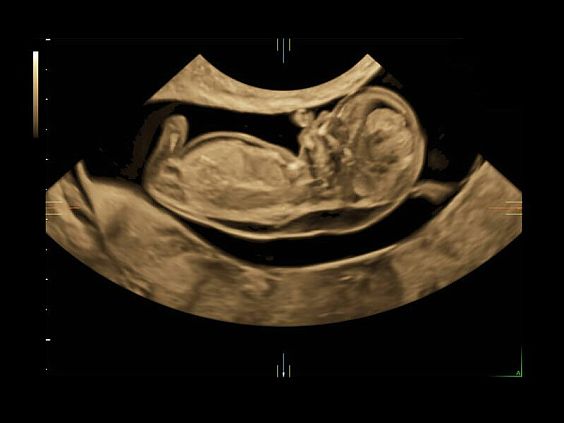

Клинические изображения

• Автоматическое определение плода в режиме 3D (SonoRenderLive) – позволяет значительно экономить время и получать изображение конечностей и лица плода в режимах 3D без артефактов и помех – система автоматически определяет границы конечностей и лица плода и выстраивает объемное изображение

Объемное сканирование Voluson — 3D/4D вашей мечты

Объемное УЗИ на Voluson E10 — это не просто потрясающе красивая картинка, это ценный инструмент получения дополнительной информации при обследовании женщин.

Voluson E10 поддерживает инновационные технологии формирования изображений — HDlive Silhouette и HDlive Flow, которые позволяют увидеть мельчайшие детали. Алгоритм SonoRenderlive упрощает рабочий процесс и дает возможность реконструировать изображение поверхностей, определяя область перехода между тканью и жидкостью.

• SonoRenderlive

• Улучшает объемную визуализацию за счет автоматического определения линии начала реконструкции при изображении поверхностей. При исследовании в режиме 4D функция SonoRenderlive непрерывно обновляет положение исходной линии с учетом движений плода.